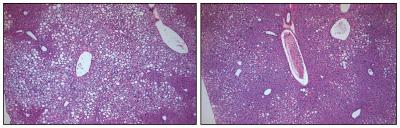

Evans' team injected doses of FGF1 into obese mice with diabetes to assess the protein's potential impact on metabolism. Researchers were stunned by what happened: they found that with a single dose, blood sugar levels quickly dropped to normal levels in all the diabetic mice.

The researchers found that the FGF1 treatment had a number of advantages over the diabetes drug Actos, which is associated with side effects ranging from unwanted weight gain to dangerous heart and liver problems. Importantly, FGF1—even at high doses—did not trigger these side effects or cause glucose levels to drop to dangerously low levels, a risk factor associated with many glucose-lowering agents. Instead, the injections restored the body's own ability to naturally regulate insulin and blood sugar levels, keeping glucose amounts within a safe range—effectively reversing the core symptoms of diabetes.